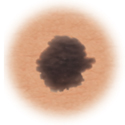

Normal mole.

Moles (nevi)

Small skin marks caused by pigment-producing cells in the skin. Moles can be flat or raised, smooth or rough, and some contain hair. Most moles are dark brown or black, but some are skin-colored or yellowish. Moles can change over time and often respond to hormonal changes.